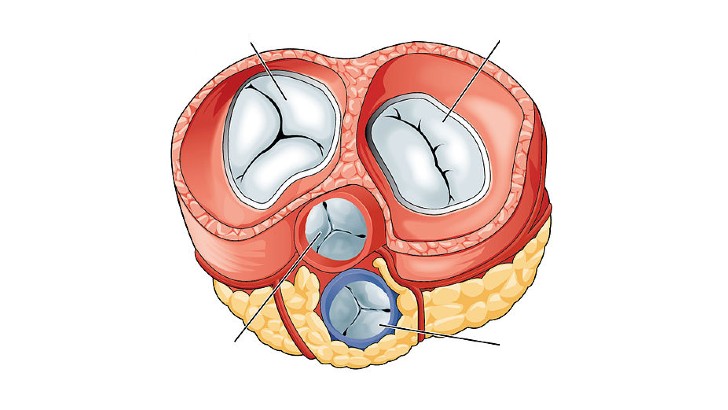

What is the name of the heart valves that ensure blood flows from the atria to the ventricles and not vice versa?

Pyloric valves

Semilunar valves

Atrioventricular (AV) valves

Ileocecal valves